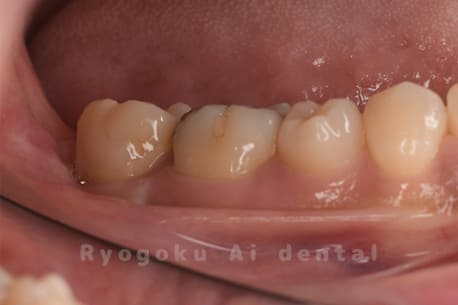

Case22

-

- 原因

- 重度カリエス

- 治療内容

- クラウンレングスニング治療

- 治療費用

- 110,000円(別途被せ物)

他院で抜歯を宣告され、当医院で保存希望でご来院された患者様です。クラウンレングスニングを行い、保存しました。大変満足されました。

<リスク・副作用>

手術後は痛み、腫れ、痺れ、青あざなどの副作用が生じます。痛みは痛み止めを処方しますが、腫れ、青あざは1週間程度生じる場合があります。また、部位によっては神経の走行が複雑で、痺れが残り、長期的にお薬を処方する場合があります。